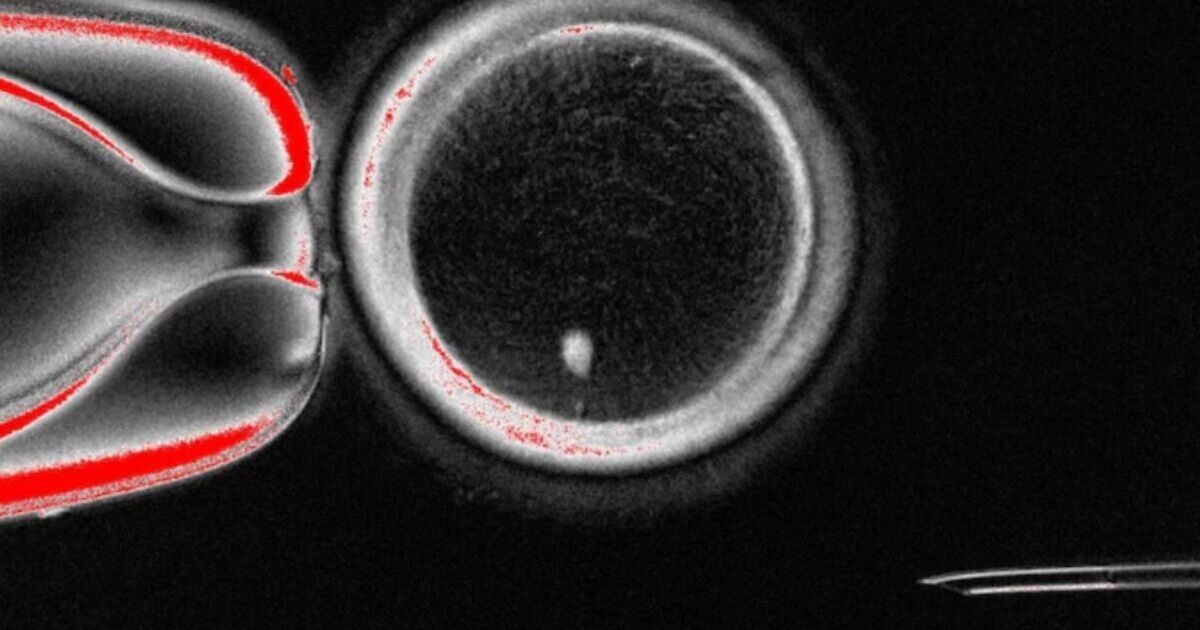

Esperti americani dell'Oregon Health & Science University affermano che gli ovuli umani ricavati dalle cellule cutanee sono pronti per la fecondazione. Quando il team ha fecondato l'ovulo con lo sperma, questo ha iniziato a crescere fino a diventare un embrione, finché l'esperimento non è stato interrotto a sei giorni, il momento in cui un embrione verrebbe trasferito nell'utero durante la fecondazione in vitro. Questa svolta consentirebbe alle donne anziane che hanno difficoltà a concepire o alle donne che non hanno ovuli per motivi medici di avere un bambino.

I ricercatori hanno fatto questa scoperta rimuovendo prima il nucleo dalle cellule cutanee normali e trasferendolo poi in un ovulo donato da cui era stato rimosso il nucleo.

Tuttavia, un grosso ostacolo è che le cellule della pelle hanno 46 cromosomi, mentre le uova ne hanno 23. Per superare questo problema, gli scienziati sono riusciti a rimuovere i cromosomi in eccesso utilizzando un processo che chiamano "mitomeiosi", che "imita la divisione cellulare naturale e fa sì che un set di cromosomi venga scartato, lasciando un gamete funzionale", hanno spiegato i ricercatori in una dichiarazione.